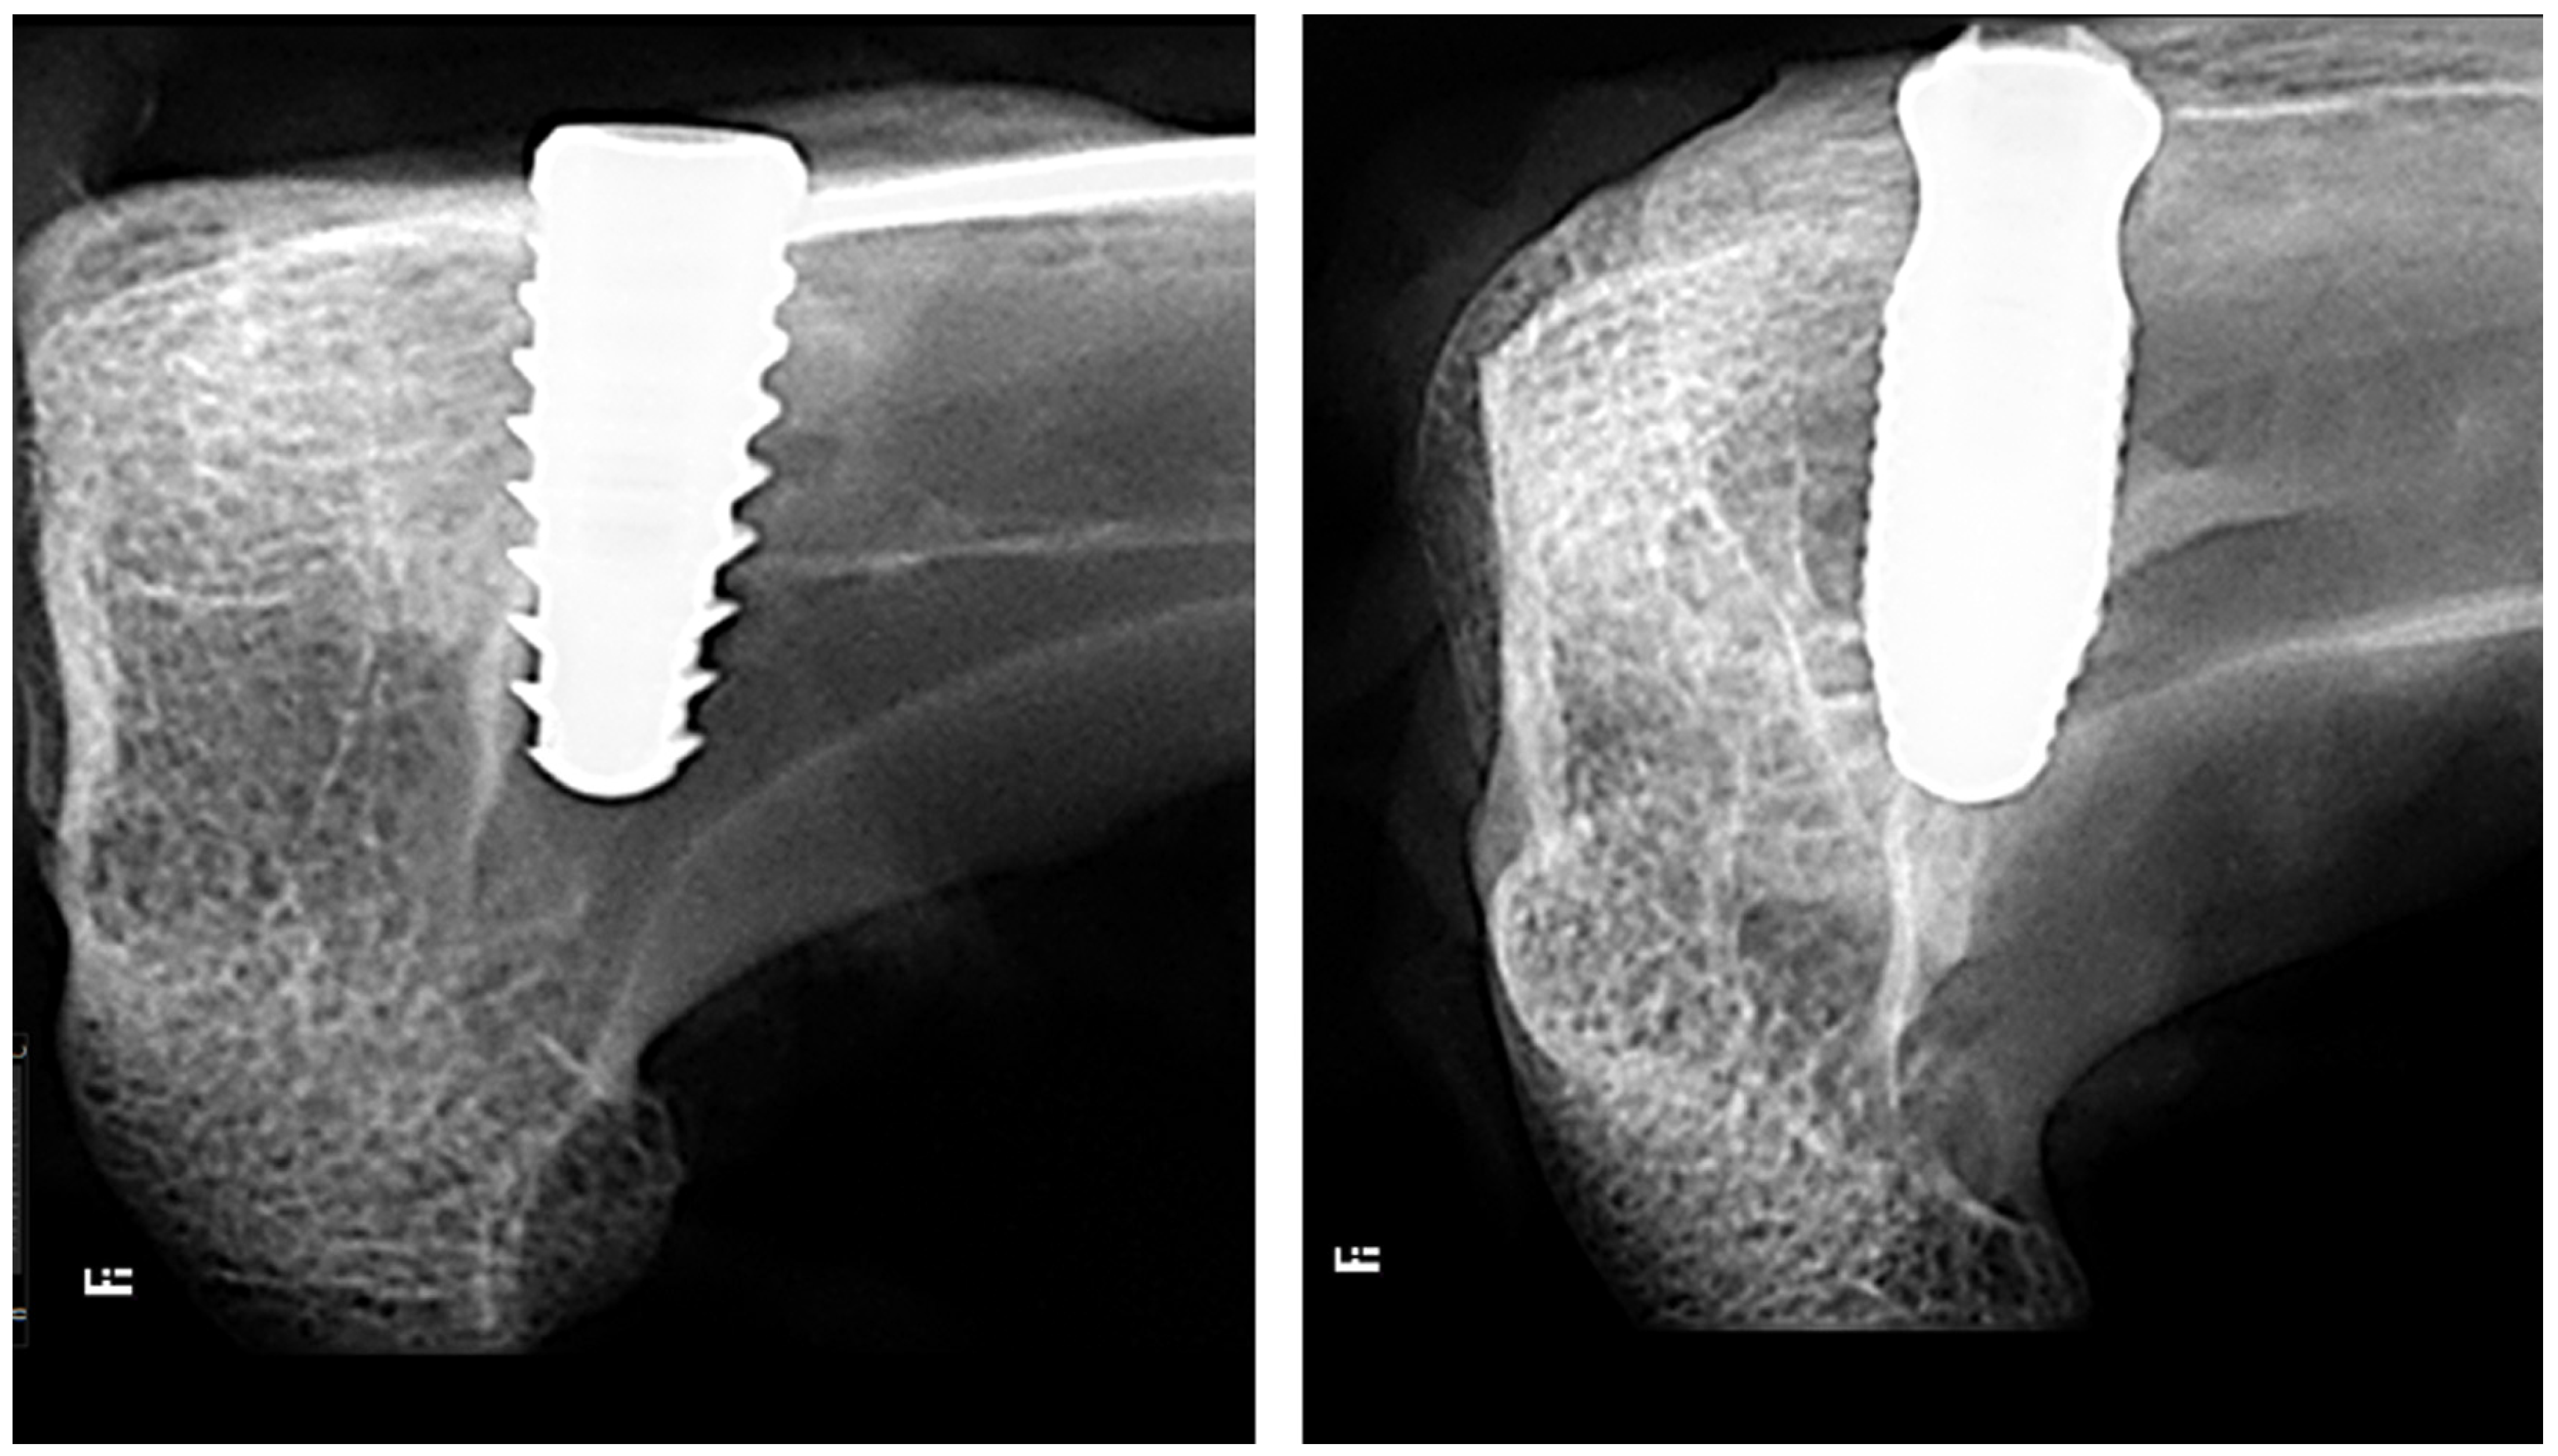

: new bone; * collagen matrix;

: medullary space).